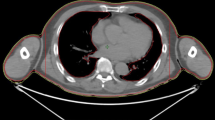

In preparation for TBI, two planning CT scans were required, because the TomoTherapy® Hi-ART II is limited to a maximal couch movement of 135 cm. These CT scans were performed using a fixation mask for the head and a vacuum cushion for the body to help stabilize the patient and prevent significant alterations in the patient’s position during CT, between CT and treatment, and during treatment. The first CT scan was performed in the cranio-to-caudal direction, and the second CT scan was performed in the caudo-to-cranial direction, both with a slice thickness of 5 mm. To correctly match these two scans and assist in treatment planning, a radio-opaque marker was placed on the patient’s upper thigh. The exact position of the marker depended on the patient’s height to ensure that neither CT scan (and thus treatment plan) exceeded the maximum length of 135 cm.

The matching of CT scans and all delineations and planning were performed using an Eclipse Treatment Planning unit (Varian Medical System, Palo Alto, CA, USA). To calculate the optimal dose for irradiating the junctional area, two treatment plans were fused and matched, with JT5 being the lowest part of the upper treatment plan and JT6 being the highest part of the lower treatment plan. The connecting area (JT4–7) was planned with 50% of the prescribed dose. Contouring of the whole body and organs at risk as well as generation of the planning target volume (PTV), sparing the lungs, were performed according to current institutional and international standards [18]. Nine patients underwent treatment planning and delivery using a helical approach (Fig. 1), and 10 patients underwent treatment planning and delivery using a static approach (Fig. 2). Both approaches used fixed jaws, a field width of 5 cm, a pitch of 0.4, and a constant feed rate fitting the pitch and prescribed dose. The modulation factors were 1.6 for the static approach and 2 for the helical approach. With the static approach, the dose was delivered from four angles, all covering the entire PTV. Treatment and planning times were equivalent between the two approaches.